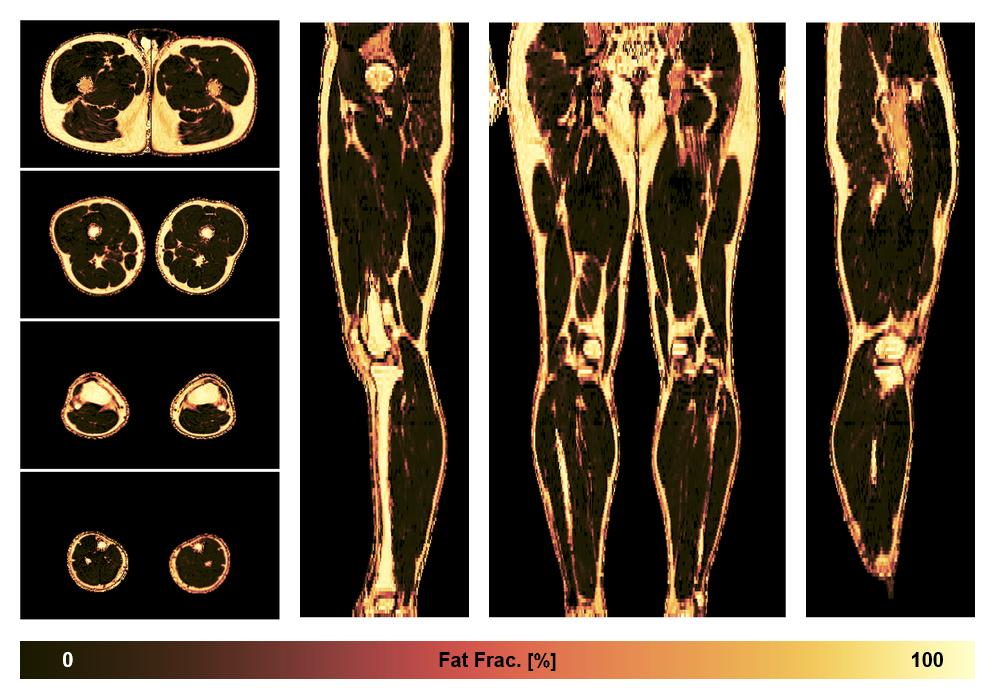

• Fat fraction

The fat fraction of the lower extremity obtained from the dixon reconstruction for muscle water fat quantification.